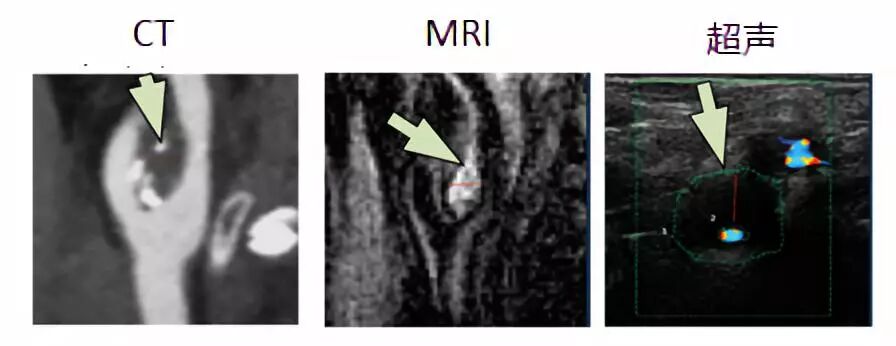

图3 斑块内出血的影像学特征(箭头指示)

斑块内出血(intraplaque haemorrhage, IPH)是脆弱的颈动脉斑块的关键特征之一,与脂质坏死核心的扩大和斑块快速进展有关。荟萃分析显示,不论是否出现症状,MRI检测到的IPH均与患者未来的卒中风险增加有关(风险比HR 4.59, 95%置信区间 CI 2.91-7.24)。MRI是检测IPH的最佳成像手段,使用常见的T1压脂序列就能轻松检测到这一变化,并且能够根据出血发生的时间,将IPH分为新鲜出血(1型)、近期出血(2型)和陈旧出血(3型)。不过,目前并没有证据表明出血的亚型与卒中风险变化之间的关系。超声和CT则不太适合检测IPH。